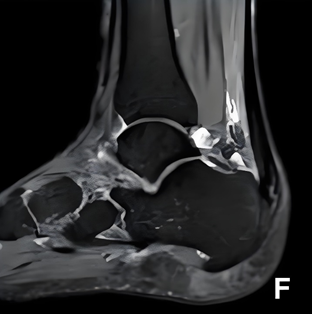

▶MRI检查:跟腱内部纤维断裂和增粗等改变,常伴有跟腱滑囊炎,对跟腱炎的诊断具有重要的意义。

图7:MRI检査可见跟腱止点处钙化增生, 跟腱滑囊炎